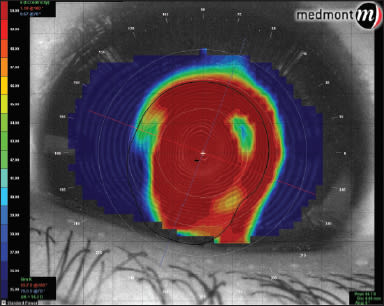

A couple of clicks later and we had customized the scale for his cornea. The sim-K readings had a steep value of about 93.00D, so we set the upper limit of the scale at 95.00D. Figure 2 shows the adjusted scaling. The steepest area of the cone is much smaller and more centralized than it appears with the default scale.

Figure 2. Topography map using customized scale.